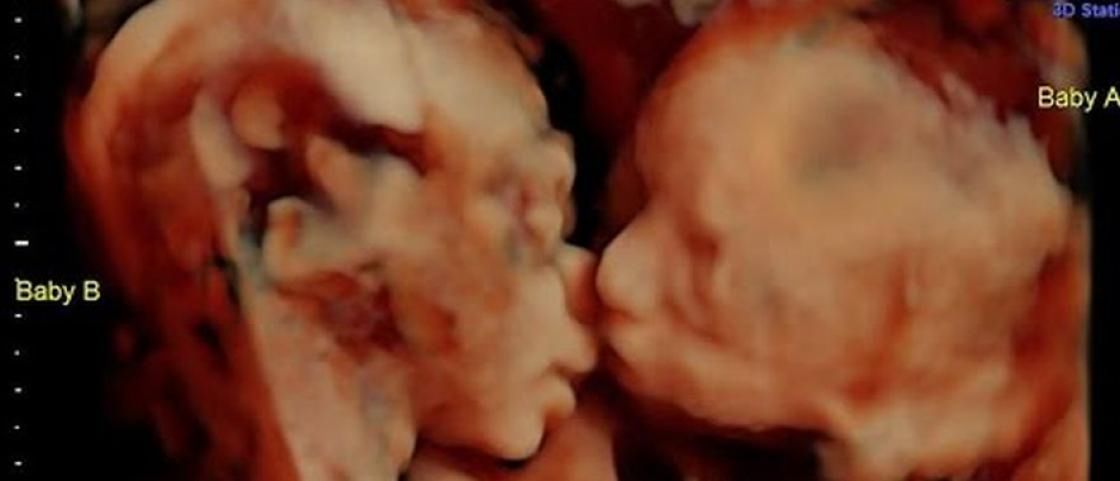

Jedno zdjęcie USG sprawiło, że te jeszcze nienarodzone bliźniaczki stały się znane na całym świecie. Przyszłymi rodzicami dziewczynek jest para mieszkająca w stanie Pensylwania w USA. Carisa Gill i Randy Good w kwietniu 2017 roku wykonali badanie ultrasonografem, podczas którego ich oczom ukazał się niezwykły widok.

Carisa Gill jest w 25. tygodniu ciąży bliźniaczej. Jej córeczki mają już nawet wybrane imiona – Callie i Isabella.

- To niezwykle ekscytujące, że możemy zobaczyć nasze córki w takiej sytuacji. Wiedziałam, że będą ze sobą blisko, ale nie sądziłam, że aż tak. To jest piękne! Już nie mogę się doczekać naszych dwóch księżniczek – powiedziała przyszła mama.

Lekarz, który wykonywał badanie również nie krył swojego zdziwienia. John Hamburg z Fetal Vision Imaging w Levitton, która specjalizuje się w badaniu dzieci w łonie matki za pomocą technologii 3D, mówi, że dziewczynki są naprawdę wyjątkowe.

– Zrobiłem już ponad 15 tys. zdjęć USG i żadne z nich nie było takie, jak to. Nigdy nie widziałem bliźniaków, którzy byli zwróceni do siebie twarzami, wyglądając jakby się całowali. W większości przypadków główka jednego dziecka jest w dole, drugiego - w górze – komentuje Hamburg i zapewnia, że zdjęcie jest w 100 proc. autentyczne.

–To jedno z najlepszych ujęć od lat! - napisali pracownicy klinki na Facebooku i pogratulowali przyszłym rodzicom. Callie i Randy uważają, że to znak, że dziewczynki będzie łączyć wyjątkowa więź i będą sobie niezwykle bliskie. Taki widok mogli zobaczyć dzięki nowym technologiom, a dokładnie USG 3D.